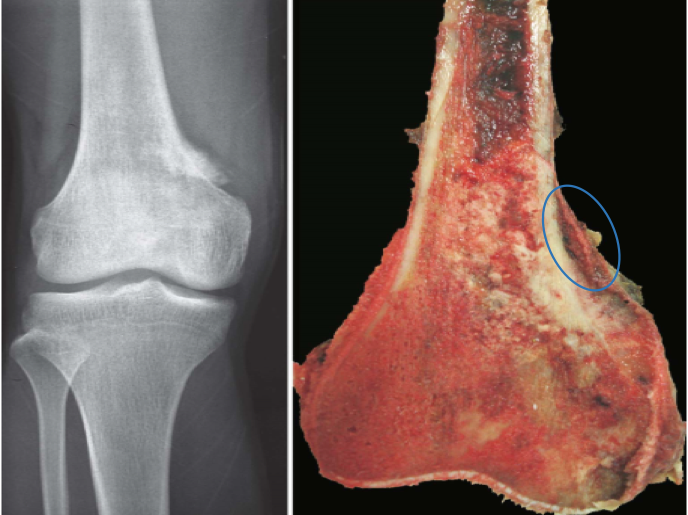

7.骨肉瘤(osteosarcoma)

特点:起源于骨母细胞,是最常见的骨恶性肿瘤。常见于青少年。好发于四肢长骨,尤其是股骨下端和胫骨上端。

(1)肉眼观:肿瘤位于长骨干骺端,呈梭形膨大,切面灰白色鱼肉状,常见出血坏死,侵犯破坏骨皮质,并可侵犯周围组织。肿瘤表面的骨外膜常被瘤组织掀起,上下两端可见骨皮质和掀起的骨外膜之间形成三角形隆起,在X线上称为Codman三角。此外,在被掀起的骨外膜和骨皮质之间可形成与骨表面垂直的放射状反应性新生骨小梁,在X线上表现为日光放射状阴影,这种现象与Codman三角对骨肉瘤的诊断具有特异性。

(2)镜下观:见瘤细胞由明显异型性的梭形或多边形肉瘤细胞组成,瘤细胞可直接形成肿瘤性骨样组织或骨组织是病理诊断骨肉瘤的最重要组织学依据。骨肉瘤内还可见软骨肉瘤和纤维肉瘤样成分。骨肉瘤呈高度恶性,生长迅速,常在发现时已经有血行转移至肺。